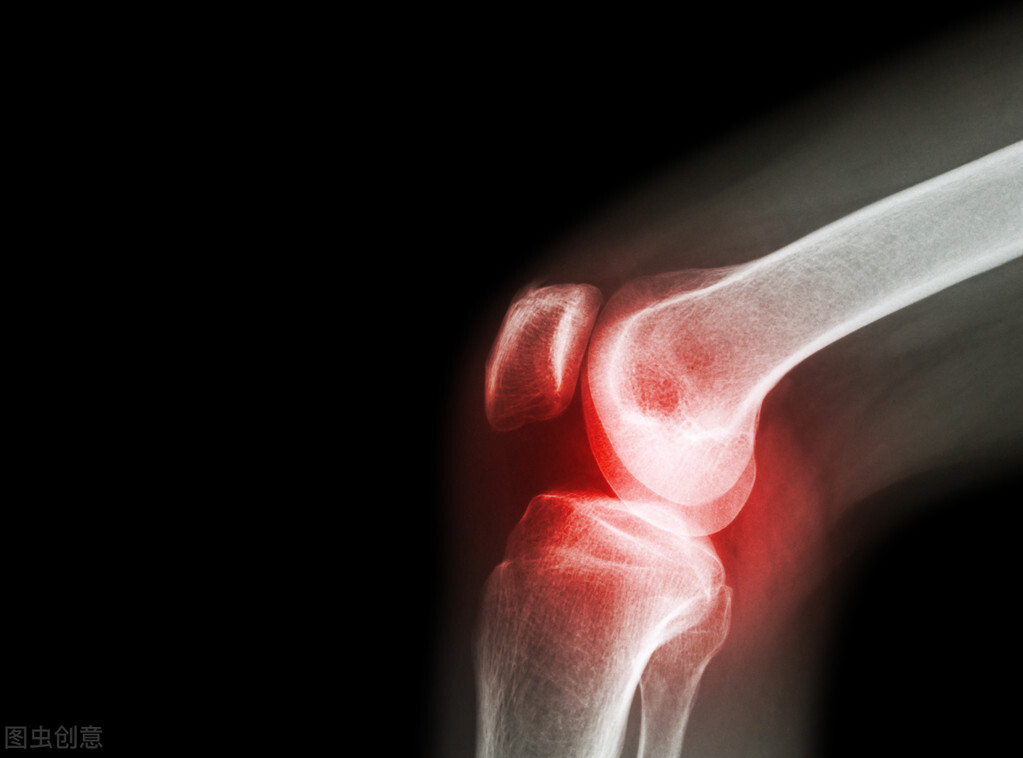

如果人们发现自己的骨头出现了风湿疾病,必须到医院进行关节影像检查、化验检查和常规检查,必须在医生的指导下选择合适的药物进行治疗。人们应该使用一些中药进行调理,能够起到活血化瘀和消炎止痛的功效,应当通过理疗等方式来帮助减少风湿疾病对骨头的伤害,比如烤灯治疗或者放射线治疗。